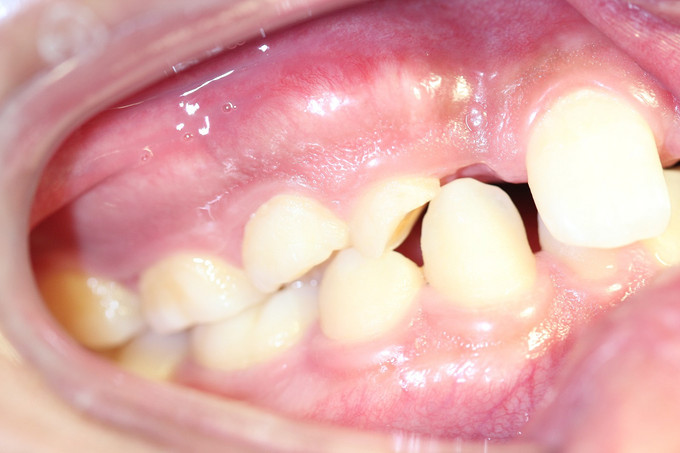

男 年龄16岁 右上恒牙2、3、4、5缺失,乳牙2、3、4、5滞留。 右下恒牙5缺失,乳牙5滞留。 左上恒牙2、3、4、5缺失,乳牙2、3、5滞留。 左下恒牙2、4、5缺失,乳牙2、5滞留。 诊断:恒牙先天缺失 治疗计划:a.乳牙治疗 b.唇系带手术 c.正畸治疗 d.种植体修复 现已经a、b两项治疗完成;因正畸难度较大,需要专家会诊共同完成!正畸治疗后再行种植修复。